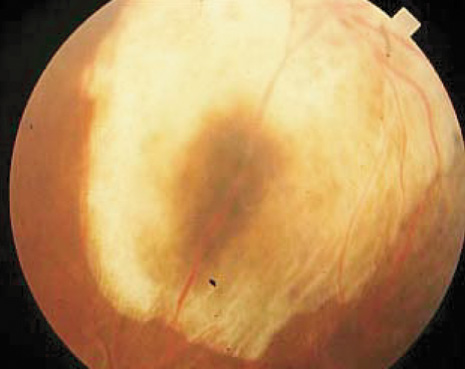

cases.24 The tumors most suitable for TTT are small, heavily pigmented melanomas

less than 3 mm in thickness, with minimal or no subretinal fluid, and

are located in the extramacular region, not touching the optic disc (Fig. 2). Tumors at the optic disc show greater recurrence and are best managed